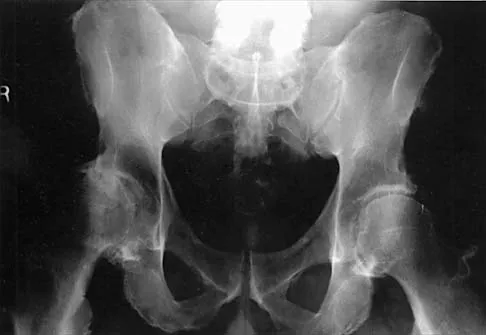

This article provides essential research regarding The Growing Problem of Osteoporosis: Your Guide to Prevention & Treatment. Osteoporosis is a condition weakening bones and causing brittle fractures, impacting quality of life with pain, disability, and even death. The problem of osteoporosis is escalating, driven by an aging population, lifestyle changes, and improved diagnosis. Addressing this serious health concern is crucial for improving public health and well-being across all ages.